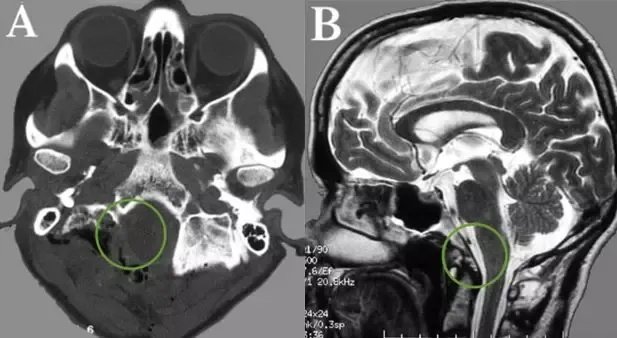

▼术后CT和MR,显示肿瘤及其被肿瘤侵犯的骨质都切除,肿瘤全切,Simpson一级切除。

术后Belle没有新发神经功能缺损,在术后二天开始肢体活动,进行康复。虽然仍有轻微的颈部疼痛,但是康复期后就好转、消失了。Belle没有出现严重的手术并发症,也没有任何后遗症会影响到未来的生活质量。

特别是手术没有脑脊液漏出或脊柱不稳定。影像检查提示肿瘤已经全切,术后伤口愈合良好,无需行放化疗。